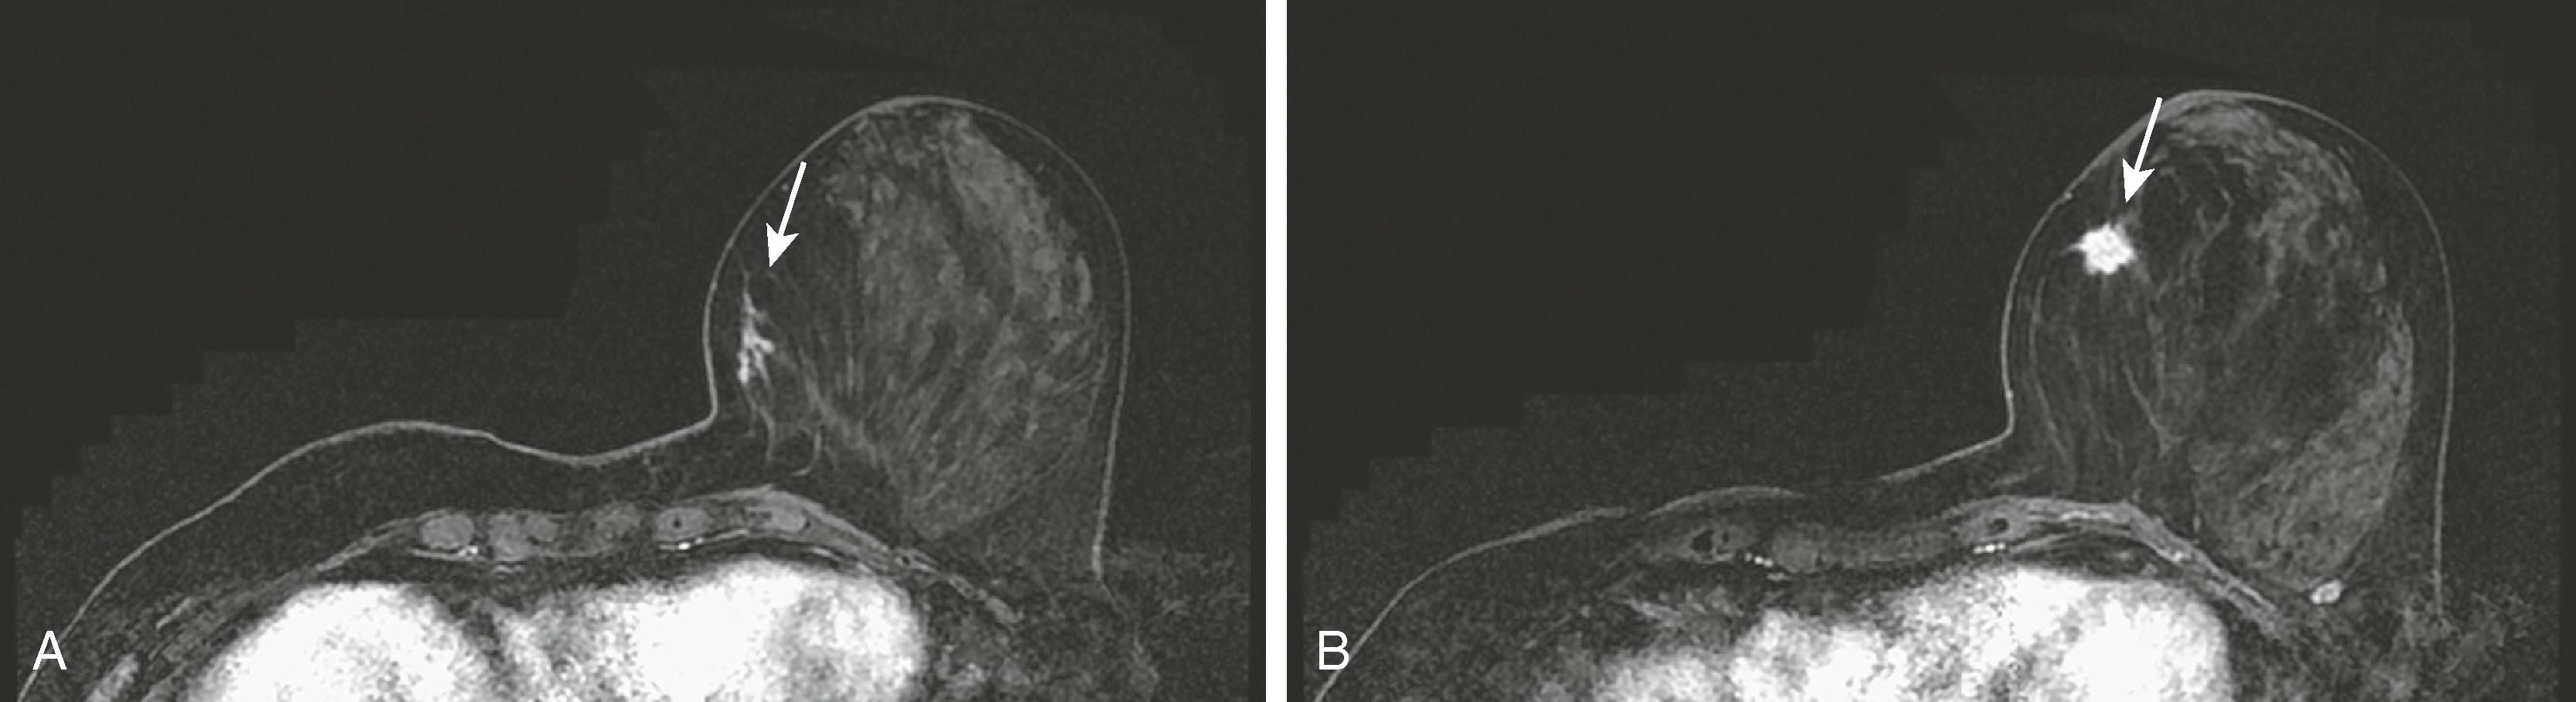

Fig. 8.34, ( A1 and A2 ) Bilateral screening mammography findings are negative. ( B ) Magnetic resonance imaging demonstrates a small enhancing lesion (arrow) in the medial left breast. ( C ) Patient returned for second-look ultrasound, which revealed a hypoechoic lesion with irregular margins (arrow) . Ultrasound-directed biopsy was performed.

MRI for high-risk screening is now an accepted test for patients with high-risk profiles such as personal history of breast cancer and strong family history in premenopausal first-degree relative. One of the sentinel papers by Kriege and coworkers found that of 1,909 high-risk women screened with clinical breast examination, mammography, and MRI, the sensitivities were 17.9%, 33.3%, and 79.5%, respectively. The conclusion was that “MRI appears to be more sensitive than mammography in detecting tumors in women with an inherited susceptibility to breast cancer.” Initially published guidelines by the American Cancer Society helped to identify patients for whom screening breast MRI would be most effective. The published guidelines stated that women who have a greater than 20% lifetime risk for the development of breast cancer should undergo yearly MRI and mammography. The topic of breast cancer screening, especially for women at high risk, has been elaborated on by others, notably Monticciolo and colleagues, with recommendations from the Society of Breast Imaging and the American College of Radiology regarding the use of mammography, breast MRI, breast ultrasound, and other technologies. Figs. 8.33 and 8.34 demonstrate two screening patients with strong family histories of breast cancer; one is a false positive and the other a true positive.